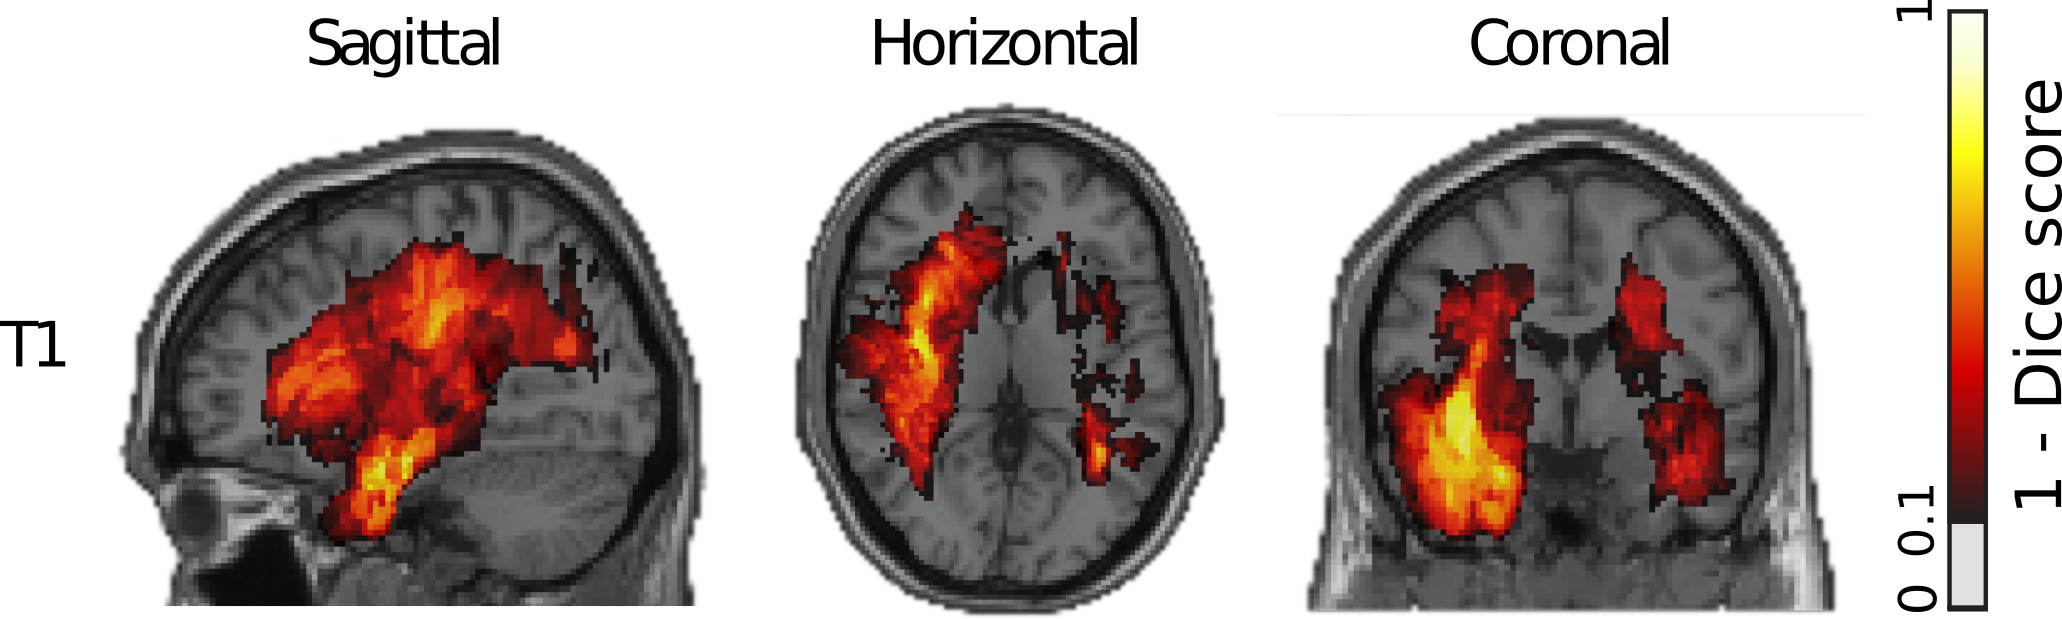

Refer to caption

Figure 5: Model error (1-Dice Score) overlaid on structural T1-template in MNI-space. Hot colors indicate high errors. The model performed well in superficial gray matter, but failed in deeper structures, especially in white matter tracts in the temporal lobe.

To examine why the model performed poorly in some few patients, we examined the model error pattern as a function brain location. We calculated the average voxel-wise Dice score for the whole tumor for all 125 validation subsets and registered them to the Colin27-MNI-template (Figure 5). We found that our model performed well in superficial gray matter (average Dice-score >>0.9), but failed to segment the tumors accurately in white matter, predominantly in deeper structures in the temporal lobes. Moreover, our model segmented the whole tumor most accurately, but struggled to differentiate the enhancing tumor from the tumor core. It especially misclassified low-grade glioma cases in which no enhancing tumor was present (Dice score of 0).